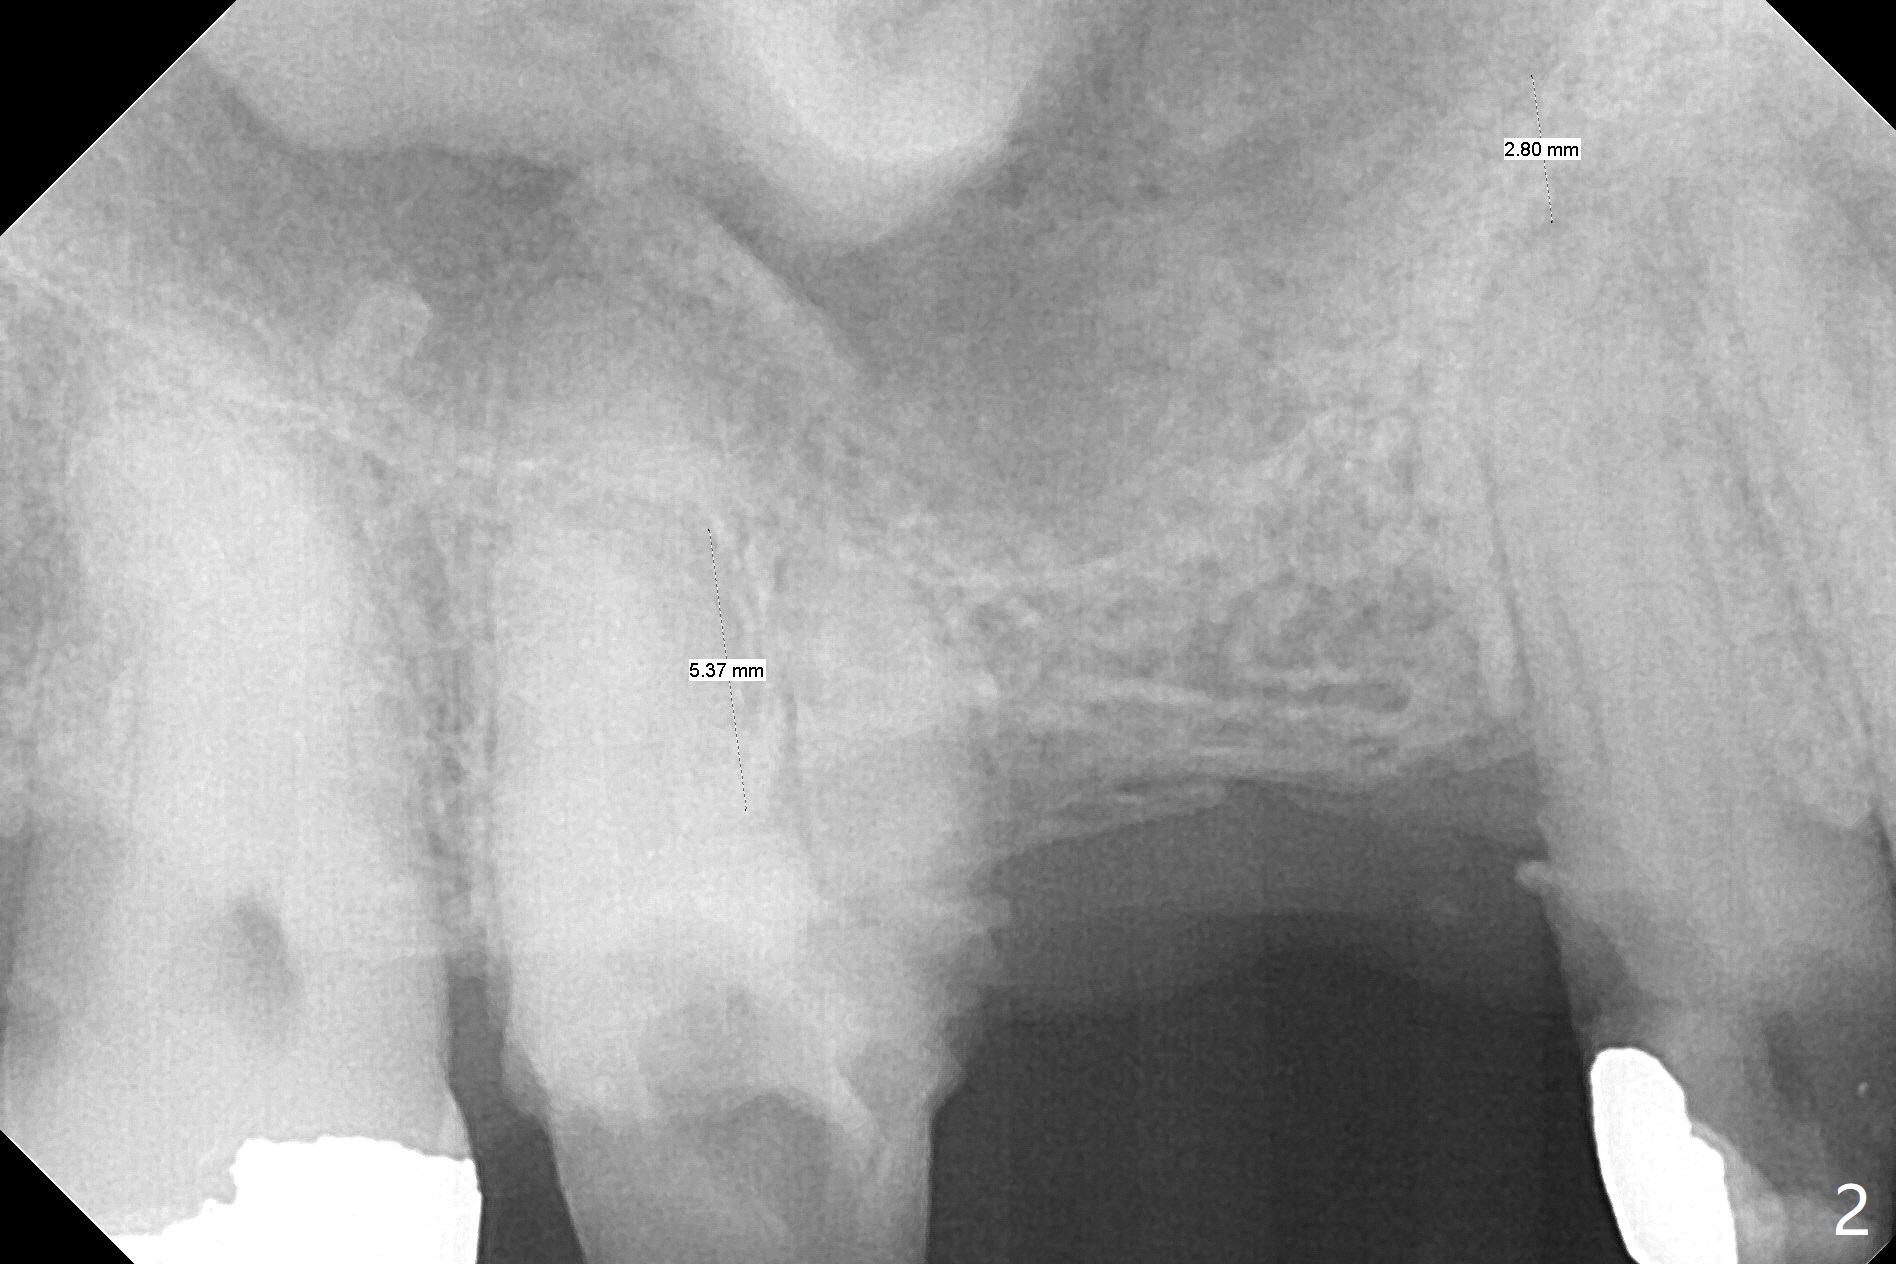

A 64-year-old man requests implant restoration after the upper FPD dislodges (Fig.1). The measurement of the septal height at #2 by PA (Fig.2) is not as precise as CBCT (Fig.11, taken 4 years earlier). There appears to be 2.8 mm bone apical to the tooth #4 (Fig.2); in contrast, the bone is more or less buccal and palatal to the root apex shown by CT (Fig.5). Furthermore CT more clearly shows apical lesions of the tooth #5 (Fig.3,4) than PA (Fig.2). In addition to pulpal test, RCT should be done for #5 prior to implant placement at #4.